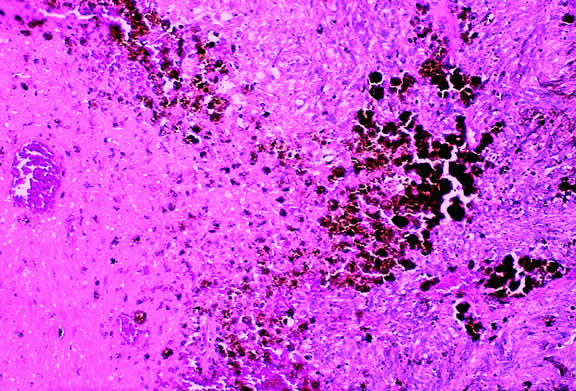

Varying degrees of necrosis may be found (Figs. 37 and 38). Necrosis tends to be more prominent in rapidly growing high-grade tumors or tumors that have had prior brachytherapy. The necrosis may be patchy and focal or may involve extensive parts or even all of the tumor. Aggregates of melanophages typically are found in the necrotic areas. Total infarction of the tumor (and other intraocular structures) may occur in eyes with severe secondary closed-angle glaucoma. As mentioned previously, melanocytoma is prone to spontaneous necrosis. The latter diagnosis should always be considered when a totally necrotic, heavily pigmented tumor is found.

Fig. 37. Focus of necrosis in choroidal melanoma. Pigmented melanophages have accumulated at interface between viable tumor and necrotic focus (below). (Hematoxylin-eosin, × 100.)

Fig. 38. Necrotic uveal melanoma. The cells of this necrotic melanoma are eosinophilic because they have lost their basophilic nuclear DNA. The cell type of a necrotic melanoma often can be ascertained if careful microscopy with an oil-immersion lens is performed. Necrotic uveal melanomas tend to behave clinically like mixed cell type melanomas. (Hematoxylin-eosin, × 250.)